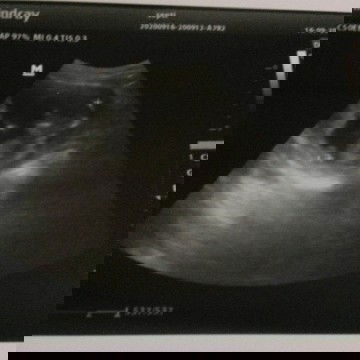

usg pertama x.. perkiraan bidan sama dokter beda. periksa kemaren senin masih 12w 5d tp kta dokter udah 13w 2d 😆